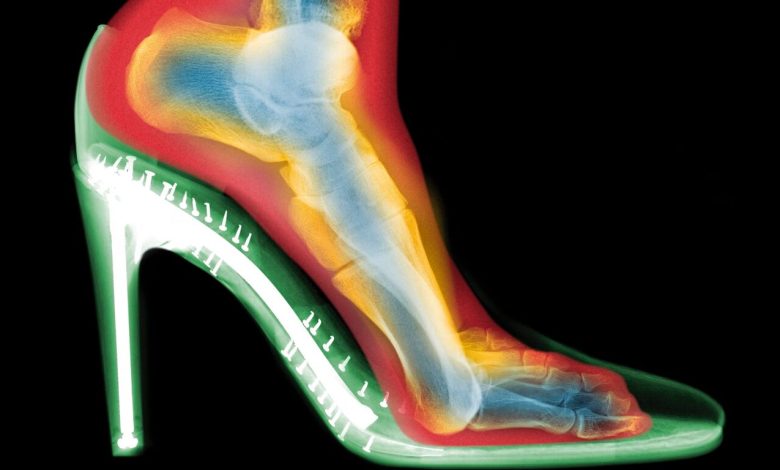

اسکنهای سهبعدی چه نشان دادند؟

گلدبرگ دو اسکن از پای یک فرد تهیه کرد: یکی بدون کفش و دیگری با کفش پاشنهبلند. تفاوتها چشمگیر بود:

فشردگی انگشتان: انگشتان پا در کفش به هم فشرده شده بودند؛

انحراف شست پا (بونیون): مفصل انگشت شست به طرف بیرون متمایل شده بود؛

انگشتان چنگالی: انگشتان کوچکتر برای حفظ تعادل، حالتی قفلشده و خمیده به خود گرفته بودند.